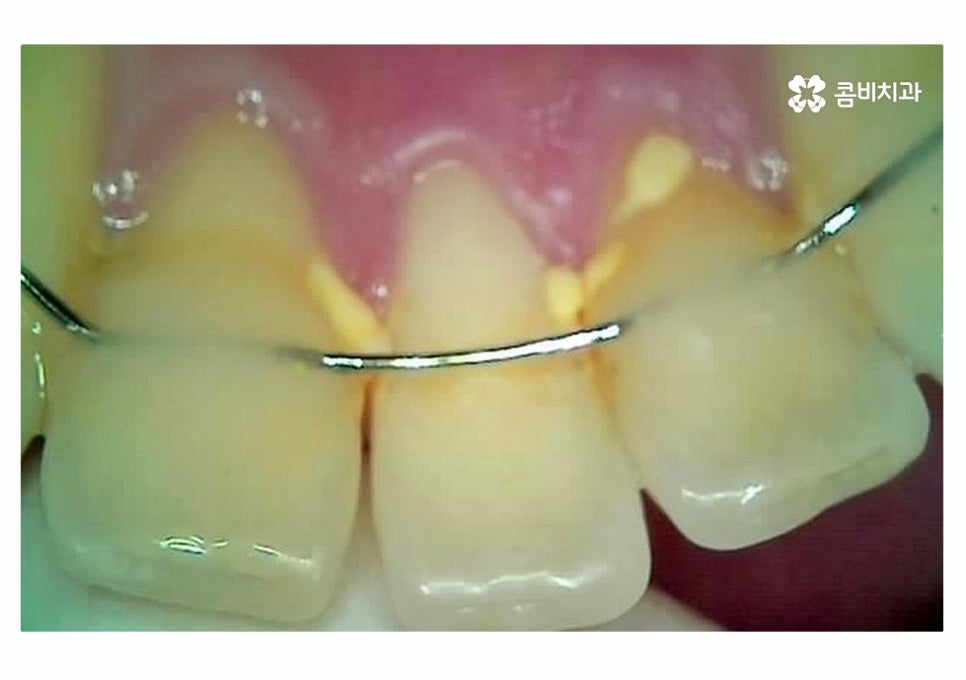

위 이미지에서 보이는 것처럼 이미 과거에

충치 떼우기 했던 부위에서 2차 충치가 생기는 사례는

치료 후 시간이 지날수록 주의해야 할 부분이라고 할 수 있어요.

이미 충치 치료를 했던 부위에 충치가 발생하는 이유는

치료 후에 시간이 지나면서 치아와 치료에 쓰인 재료 (레진, 아말감 등)

사이에 틈이 발생하거나 미세하게 크랙이 생기면서 2차 충치가

생길 수 있고 재료의 수명은 개인마다 차이가 있을 수 있기 때문에

정기적으로 검진을 받지 않으면 교체 시기를 놓치는 경우가 종종 있는데요.